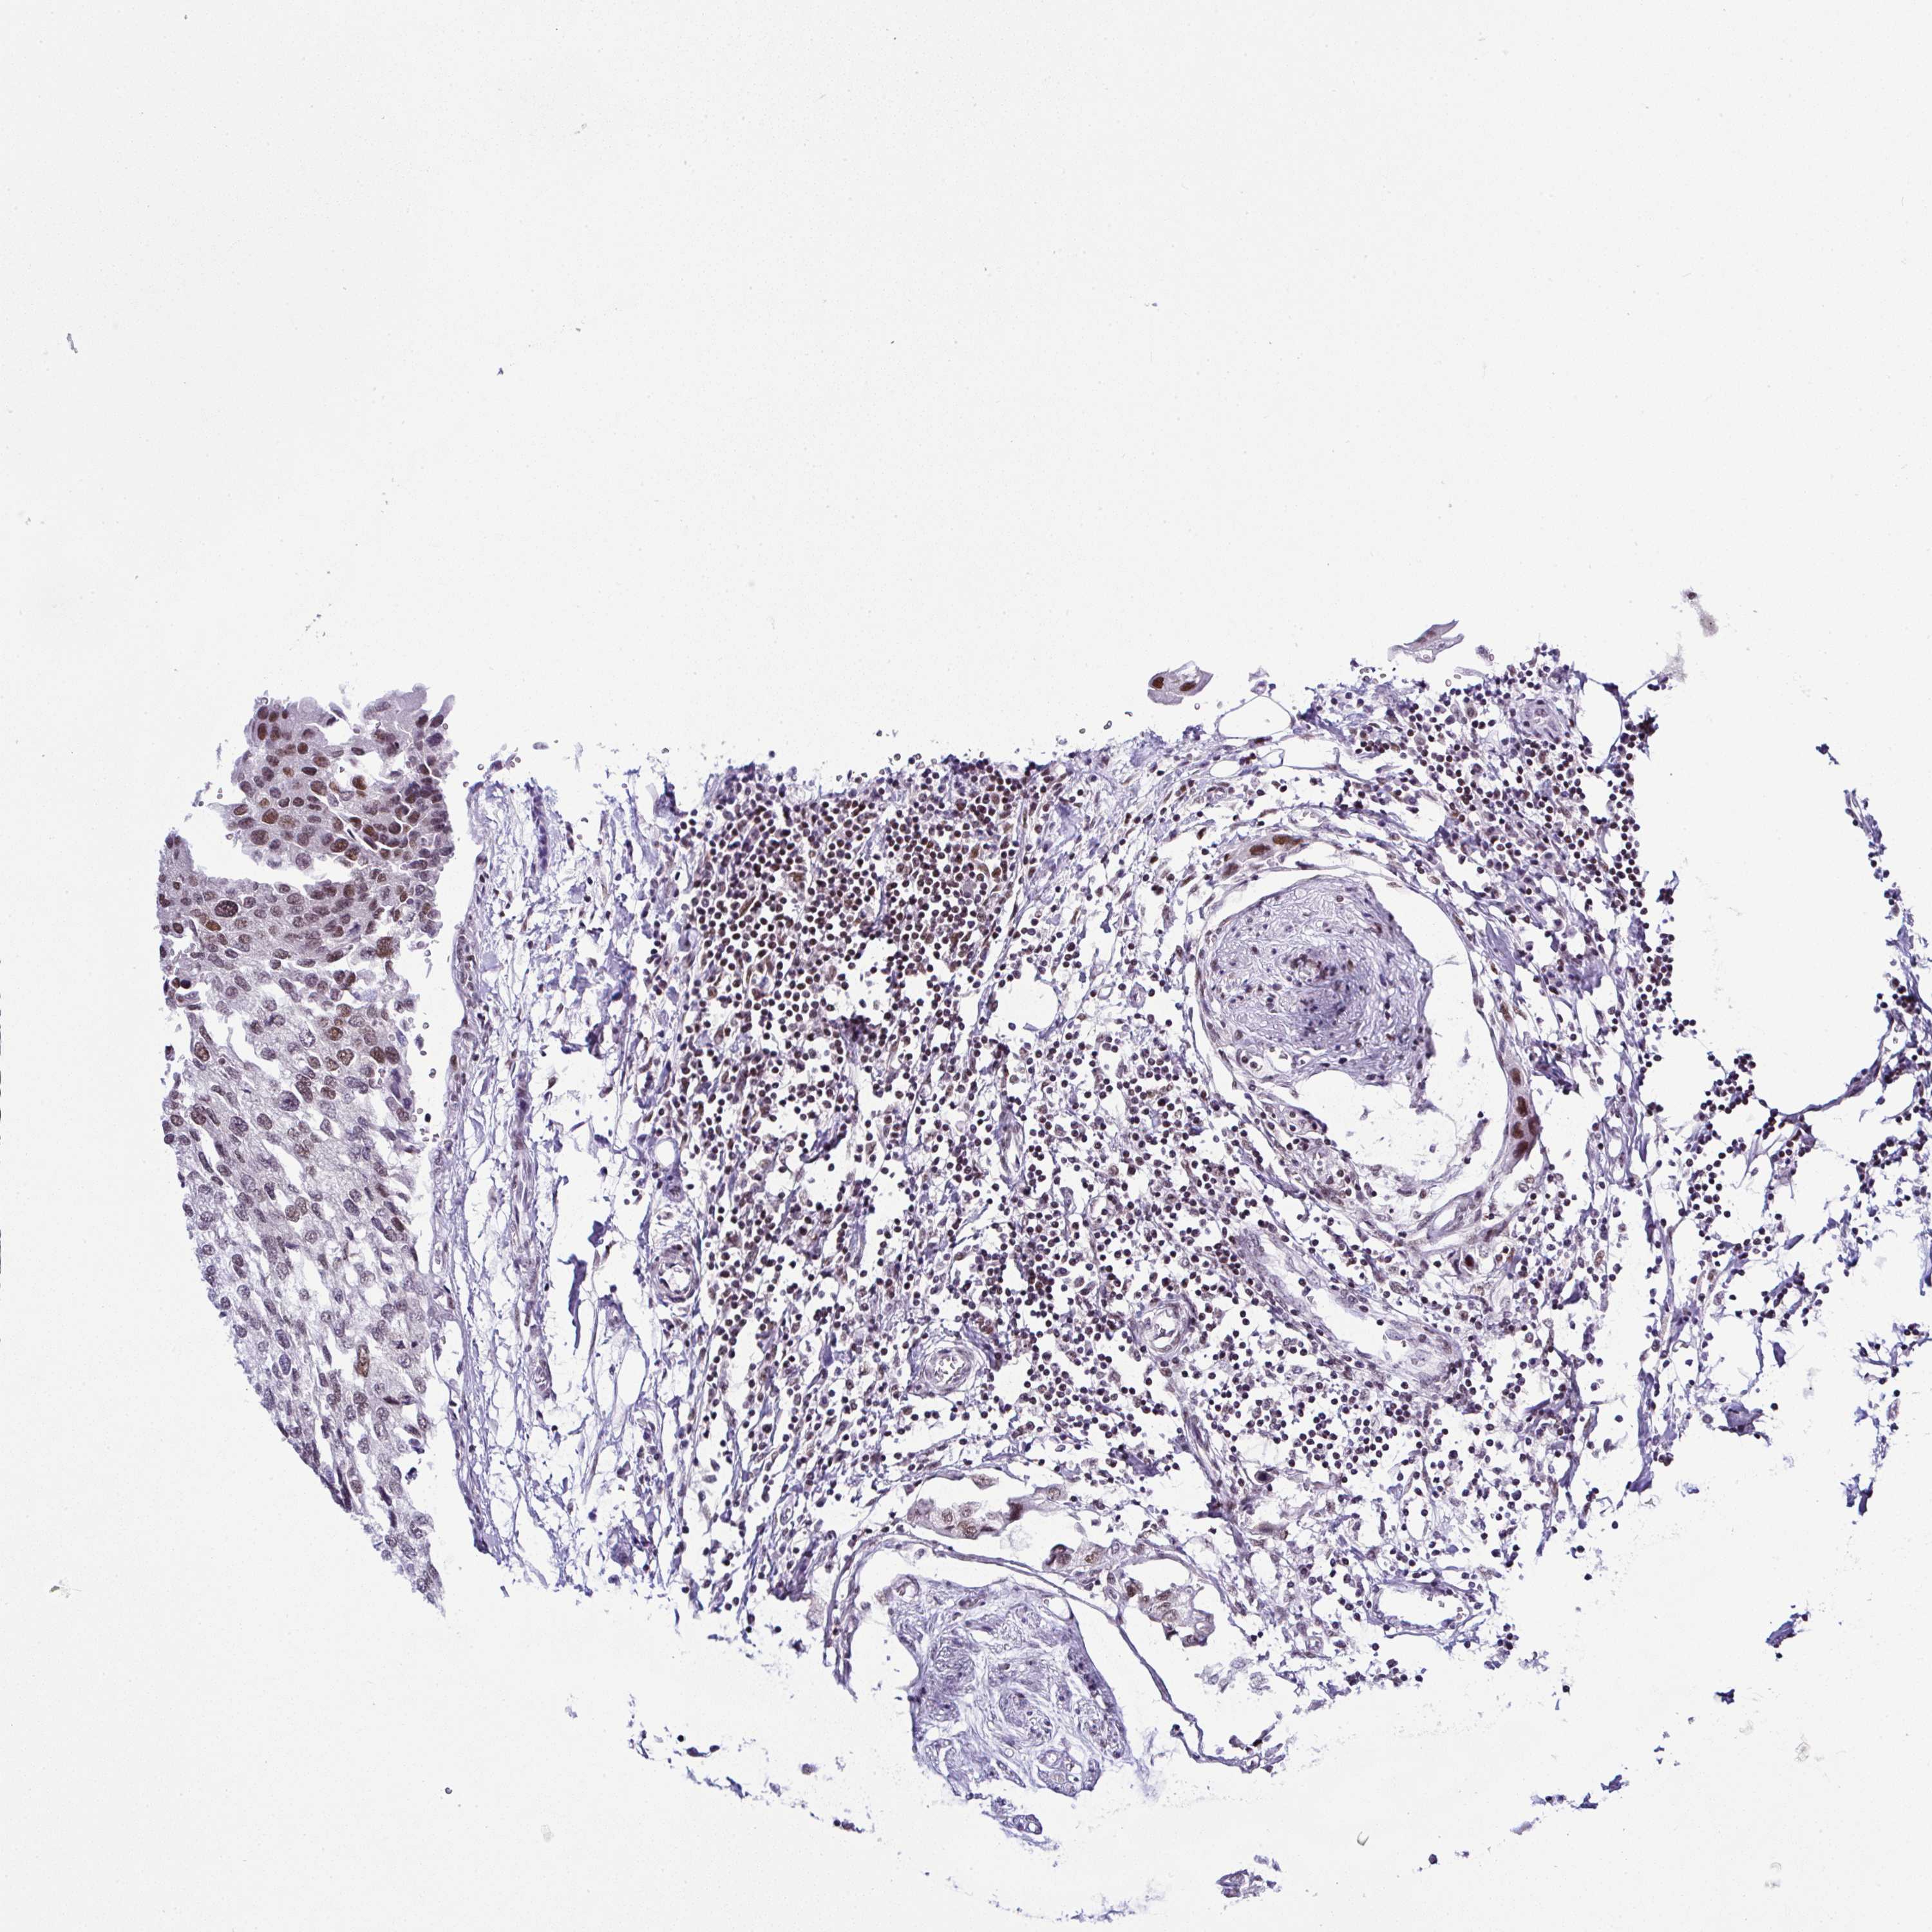

UROTHELIAL CANCER - Protein expressioni

A mouse-over function shows sample information and annotation data. Click on an image to view it in a full screen mode. Samples can be filtered based on level of antibody staining by selecting one or several of the following categories: high, medium, low and not detected. The assay and annotation is described here.

Antibody stainingi

Antibody staining in the annotated cell types in the current human tissue is reported as not detected, low, medium, or high, based on conventional immunohistochemistry profiling in selected tissues. This score is based on the combination of the staining intensity and fraction of stained cells.

Each image is clickable and will lead to virtual microscopy that enables deeper exploration of all samples and also displays staining intensity scores, fraction scores and subcellular localization as well as patient and tissue information for each sample.

Antibody HPA050785

Antibody HPA055308

Staining

High

Medium

Low

Not detected

Intensity

Strong

Moderate

Weak

Negative

Quantity

>75%

75%-25%

<25%

None

Location

Nuclear

Cytoplasmic/membranous

Cytoplasmic/membranous,nuclear

Urothelial carcinoma, High grade

Urothelial carcinoma, Low grade

Urothelial carcinoma, NOS